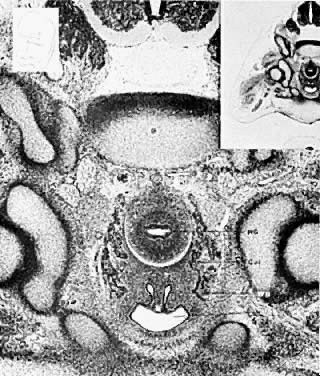

The mesonephric ducts connect with the urogenital sinus, but by the fifth week of fetal life the ureteric buds have appeared on either side of the müllerian tubercle and the metanephrogenic mass of cells (the future kidney) appears. At this time the primordial germ cells are migrating from the hindgut to form the primitive gonads along the urogenital ridge. The kidneys develop in the pelvis, beginning as a metanephrogenic mass of intermediate mesoderm around the ureteric bud. As the kidneys develop they migrate toward the head of the embryo, chiefly as a result of the growth of the embryo caudal to the kidneys. The kidneys are supplied by arteries and veins at successively higher levels as they move cephalad from the pelvis. The ureters are elongating at the same time and the kidneys rotate so that the hila come to face the midline. At the same time the mesonephric system is undergoing degeneration (Fig. 8, Fig. 9, Fig. 10, Fig. 11 and Fig. 12).

Fig. 8. Composition of urogenital ridges. Embryo 6508, 36–3-3; 7.3 mm, 41/2 weeks. Bilateral bulges from urogenital ridges (UGR) in dorsomedial wall of coelomic cavity on either side of mesentery (Mesen) of gut. Urogenital ridges (UGR) give rise to mesonephros, ovary, and metanephros. Mesonephric (wolffian) vesicles (MV) and ducts (WD) are completed, and gonadal anlages (G) are evident as masses of mesenchyme covered by thickened coelomic epithelium medial to mesonephric apparatus (M) (×30). (From Dougherty CM: Surgical Pathology of Gynecologic Disease. New York: Harper & Row, 1968.)

Fig. 9. Partition of cloaca. Embryo 8789, 17–1-3; 11.7 mm, 5 weeks. Partition of cloaca (C1) occurs when hindgut (HG) joins urogenital sinus (UGS), leaves space for urorectal fold (URF) which eventually divides sinus, and separates ventral compartment from rectum. Urogenital sinus is continuous with allantois, lower part of which will form bladder (V). Cul-de-sac (Cul) of coelomic cavity is seen as slit between hindgut and urogenital sinus (× 15). (From Dougherty CM: Surgical Pathology of Gynecologic Disease. New York: Harper & Row, 1968.)

Fig. 10. Mesonephric ducts join urogenital sinus. Embryo 8553, 95–2-1; 22 mm, 6 weeks. Cross-section near caudal end demonstrates junction of mesonephric ducts (WD) with dorsal wall of urogenital sinus (UGS). Hindgut (HG) lies behind this confluens and is separated by a caudal extension of coelomic cavity, pouch of Douglas (Cul). Müllerian ducts have not extended this far caudally yet (×15). (From Dougherty CM: Surgical Pathology of Gynecologic Disease. New York: Harper & Row, 1968.)

Fig. 11. Mesonephric ducts join urogenital sinus. Embryo 5422, 32–1; 27 mm, 6½ weeks. Caudal region is depicted in this sagittal section just off midline and shows mesonephric duct (WD) opening into urogenital sinus (UGS). This point is used as arbitrary boundary mark between vesicourethral portion cephalad and definitive urogenital sinus (pars pelvina) caudally. Rectum ( R ) has already been partitioned by urorectal fold (URF) extending to cloacal membrane, and proctodeum (Pr) has opened. Caudal extension of coelomic cavity forms cul-de-sac of Douglas (Cul). Transverse septum (TrS) of pelvis is seen in cross-section (×15). (From Dougherty CM: Surgical Pathology of Gynecologic Disease. New York: Harper & Row, 1968.)

Fig. 12. Müllerian ducts reach urogenital sinus. Embryo 6573, 74–3-2; 31.5 mm, 7 weeks. Mesonephric ducts (WD) open into urogenital sinus (UGS), while müllerian ducts (MD) occupy medial position in this area and do not yet open into sinus. Hindgut (HG) and pouch of Douglas (Cul) are behind urogenital sinus (×45). (From Dougherty CM: Surgical Pathology of Gynecologic Disease. New York: Harper & Row, 1968.)